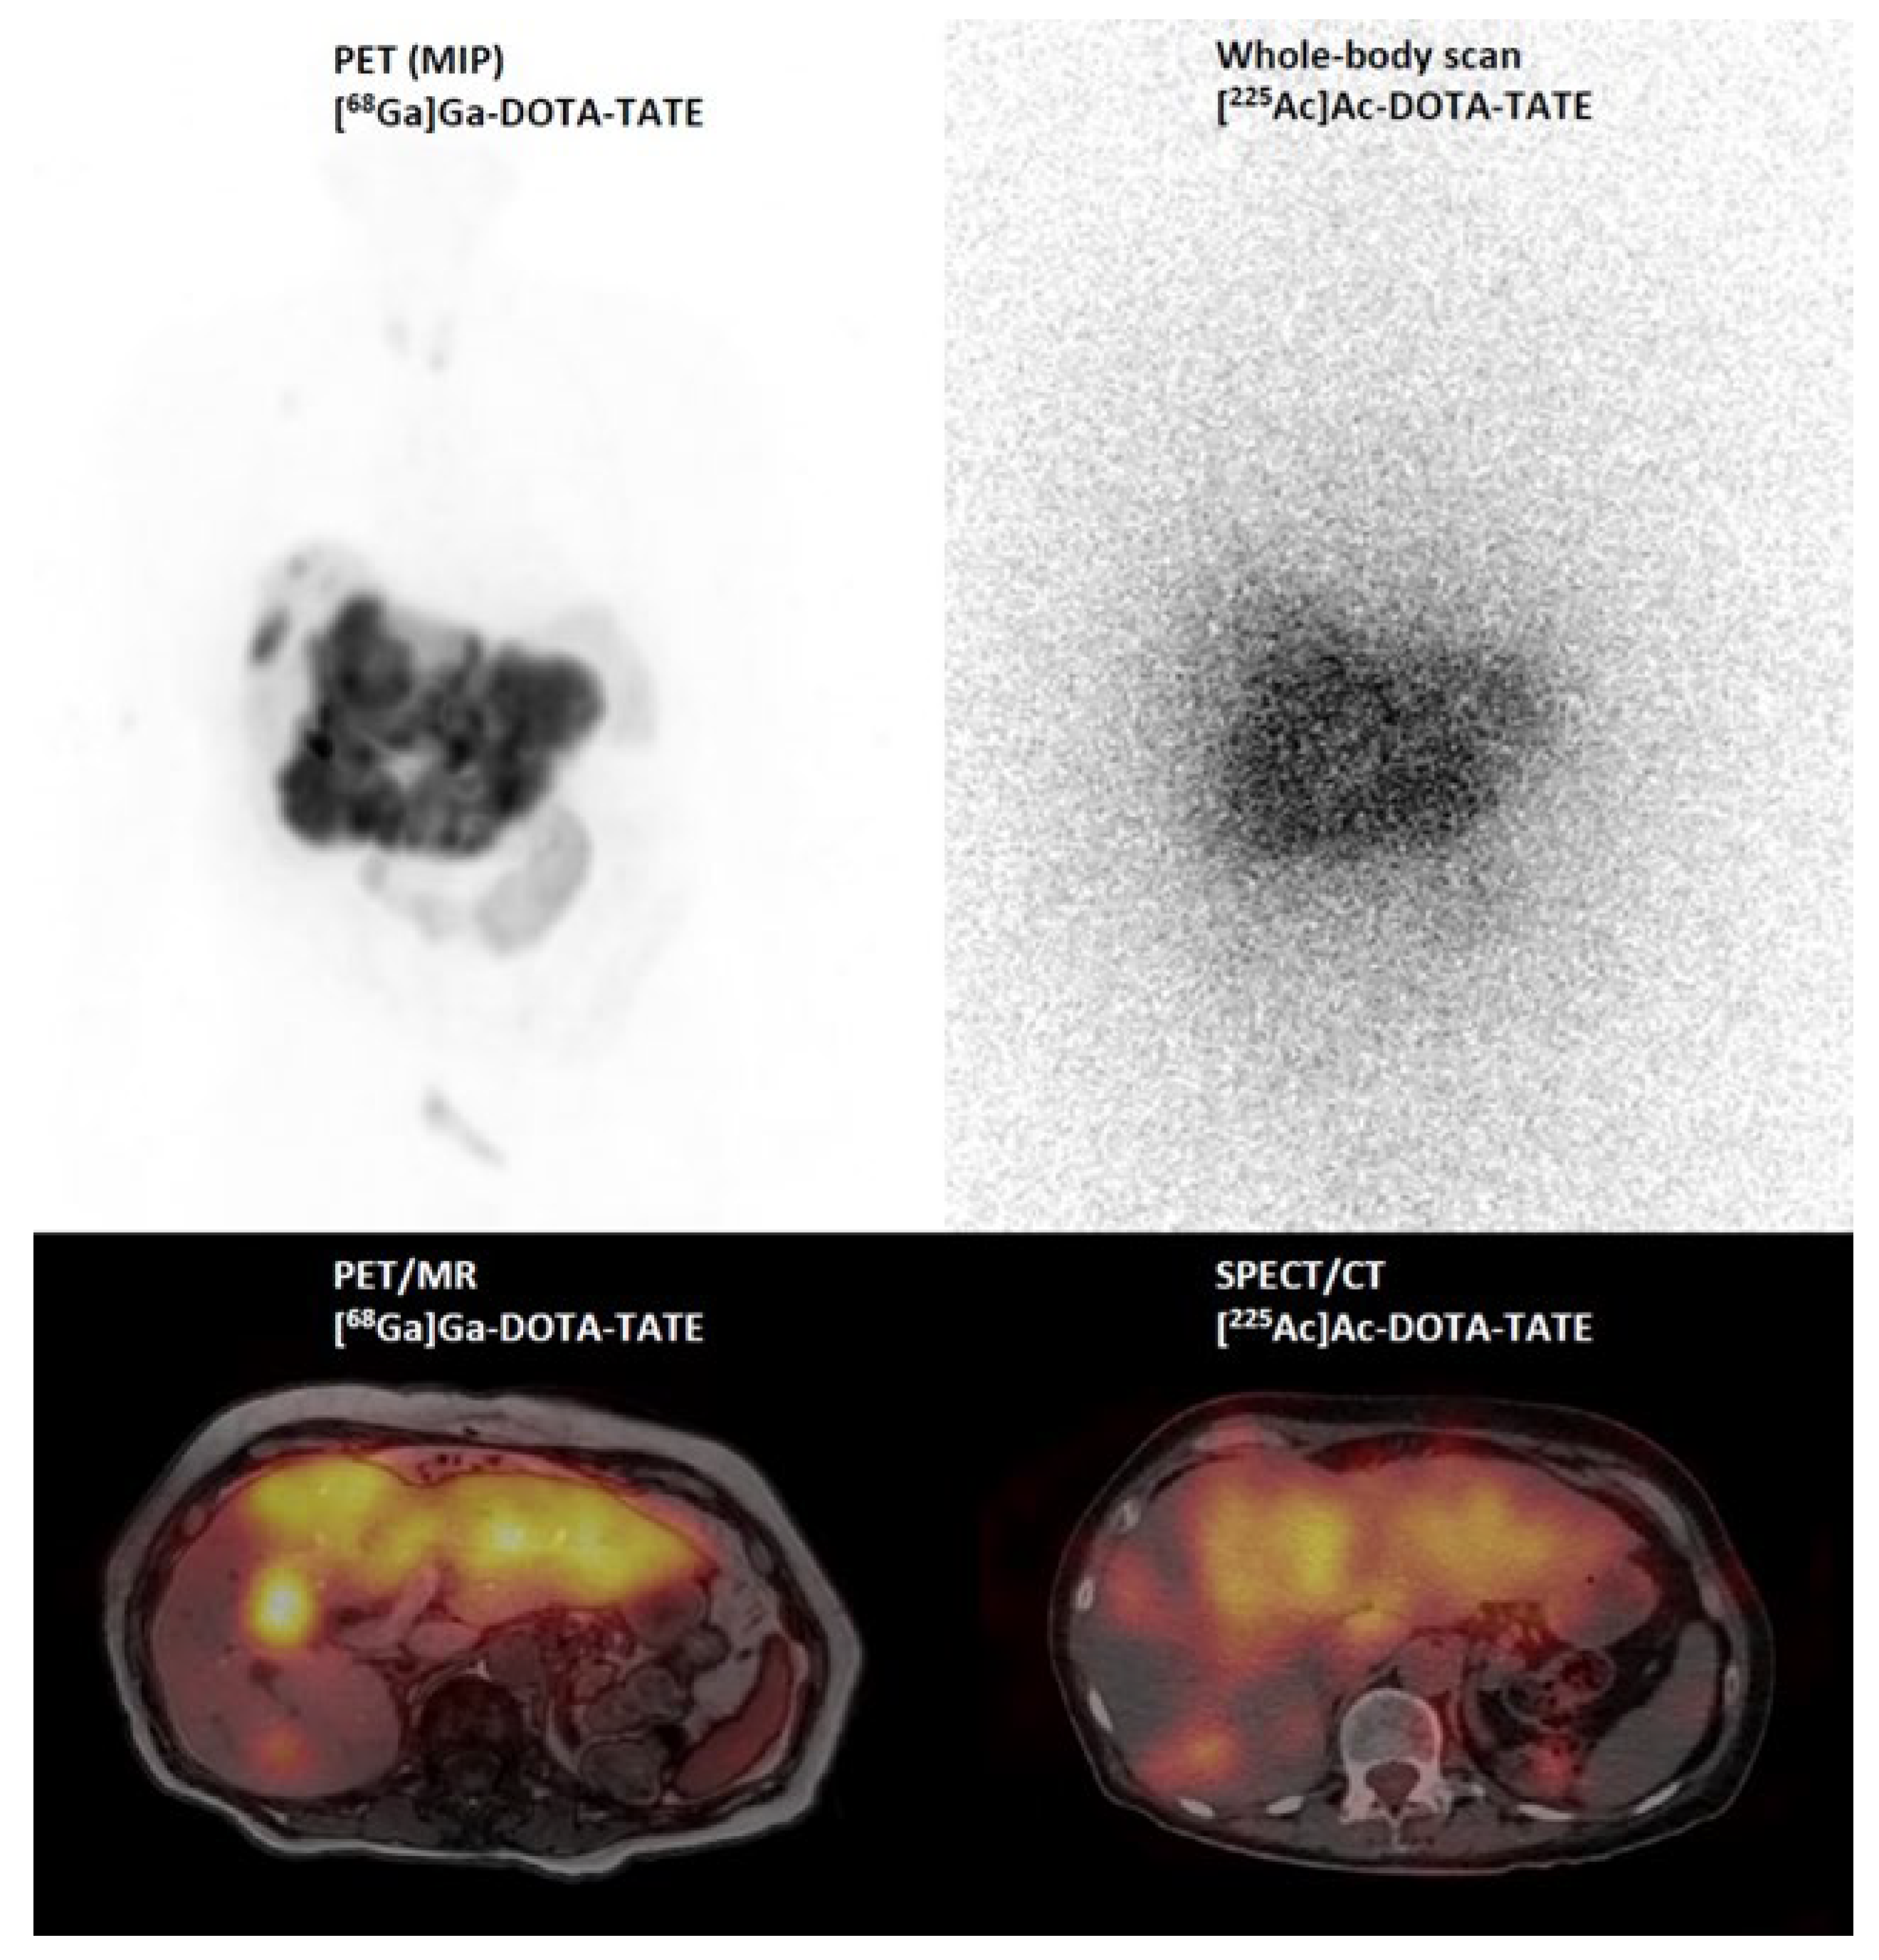

- Demirci, E.; Alan Selcuk, N.; Beydagi, G.; Ocak, M.; Toklu, T.; Akcay, K.; Kabasakal, L. Initial Findings on the Use of [225Ac]Ac-DOTATATE Therapy as a Theranostic Application in Patients with Neuroendocrine Tumors. Mol. Imaging Radionucl. Ther. 2023, 32, 226–232. [Google Scholar] [CrossRef]

- Miederer, M. Alpha emitting nuclides in nuclear medicine theranostics. Nuklearmedizin 2022, 61, 273–279. [Google Scholar] [CrossRef]